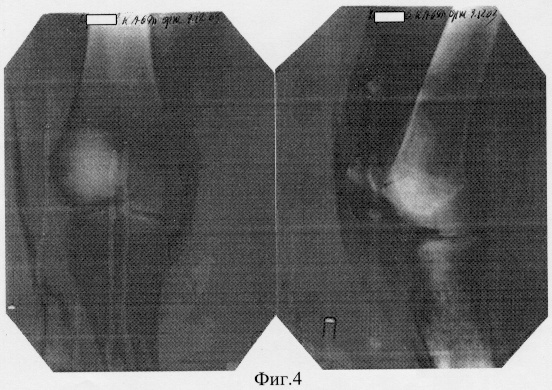

11.12.2003 г. пациент выписан в удовлетворительном состоянии в гипсовом туторе. На контрольных рентгенограммах взаимосоотношения в правом коленном суставе правильные (фиг.4 – состояние после операции).